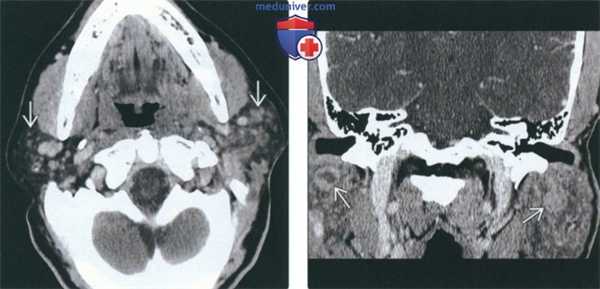

(Слева) КТ с КУ, аксиальная проекция. В обеих околоушных железах визуализируются солидные образования с четкими контурами. И хотя метастазы и лимфома могут выглядеть точно так же, гипертрофия небных миндалин позволяет заподозрить лимфоэпителиальное поражение или хроническую лимфаденопатию околоушных лимфоузлов при ВИЧ.

(Справа) КТ с КУ, единичная киста в левой околоушной железе, разделенная внутренней перегородкой. И хотя при доброкачественном лимфоэпителиальном поражении обычно обнаруживается сразу несколько образований, иногда они могут быть и единичными. В такой ситуации может быть выставлен неверный диагноз - киста первой жаберной щели.

(Слева) КТ с КУ, аксиальная проекция у пациента с объемным образованием шеи слева. Плотность обеих околоушных желез увеличена, в правой железе определяется многокамерная киста, в левой - смешанное кистозно-солидное образование.

(Справа) КТ с КУ, аксиальная проекция, этот же пациент. Определяется единичный увеличенный околоушной узел слева и гипертрофия небных миндалин. По результатам КТ пациенту было рекомендовано обследование на ВИЧ, результат оказался положительным.

(Слева) На аксиальной КТ с КУ визуализируются хорошо отграниченные солидные контрастиру-ющиеся очаги в обеих околоушных железах. Метастазы и лимфома могут выглядеть аналогично, но гипертрофия миндалин позволяет предположить ДЛЭП или персистирующую лимфаде-нопатию околоушных желез, обусловленную ВИЧ.

(Справа) На аксиальной КТ с КУ в левой околоушной железе визуализируется солитарное образование, разделенное перегородками. ДЛЭП обычно являются множественными, но возможны и солитарные поражения.

(Слева) На аксиальной КТ с КУ визуализируются множественные мелкие контрастирующиеся очаги с диффузным поражением обеих околоушных желез, характерные для персистирующей генерализованной паротидной лимфаденопатии. Данные очаги представляют собой увеличенные лимфоузлы.

(Справа) На корональной реформатированной КТ с КУ у пациента с ВИЧ определяются очаги в обеих околоушных железах, образованные кистозным и солидным компонентами, сопоставимые с ДЛЭП при ВИЧ.